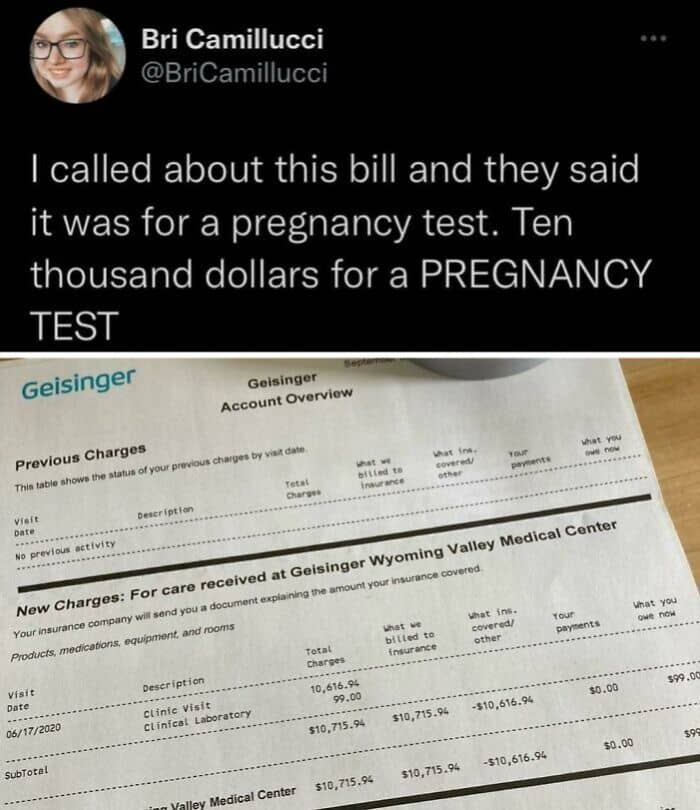

#49 This Is What $10,000 Looks Like Under The American Health Care System